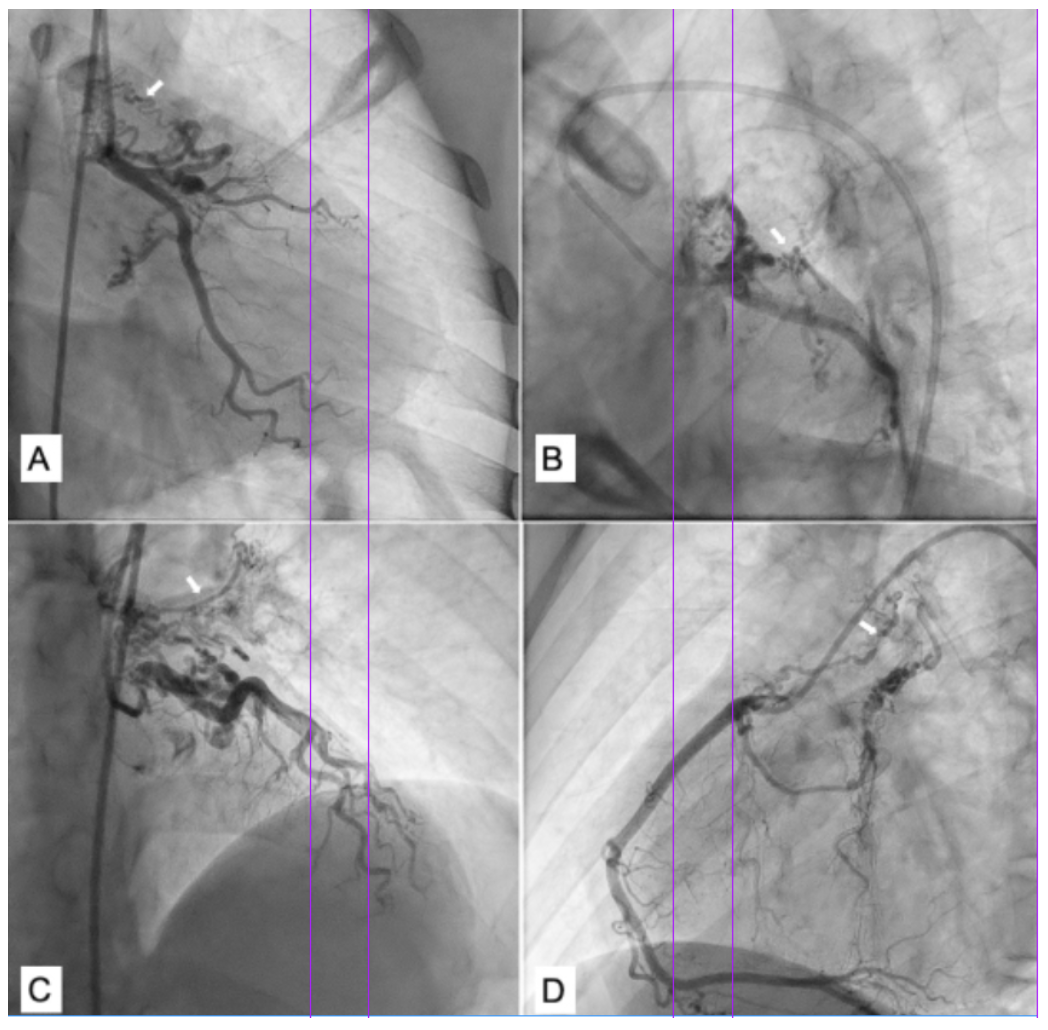

A 19-year-old male presented with history of cyanosis noted since early childhood, dyspnea, and angina on exertion New York Heart Association class II for the past 3 years. Physical examination revealed central cyanosis, pan digital grade 3 clubbing, saturation of 74%, and a grade 3 ejection systolic murmur in the left 3rd intercostal area. Echocardiography showed a large non restrictive ventricular septal defect with severe pulmonary stenosis and aortic override, suggestive of tetralogy of Fallot (TOF). Computed tomography (CT) angiography confirmed the diagnosis of TOF and showed the presence of multiple aortopulmonary collaterals (APCs) arising from bilateral subclavian arteries, coronaries, and aorta with presence of dual left anterior descending artery (LAD) with dominant LAD from the right coronary artery (RCA) (Figure 1). CT angiography nicely depicted the type 3 APCs arising from both the coronaries supplying bilateral lungs with delineation of dual LAD (Figure 2 and Video 1). Pulmonary arteries were well developed. The patient is planned for intracardiac repair of TOF along with surgical ligation of the APCs.